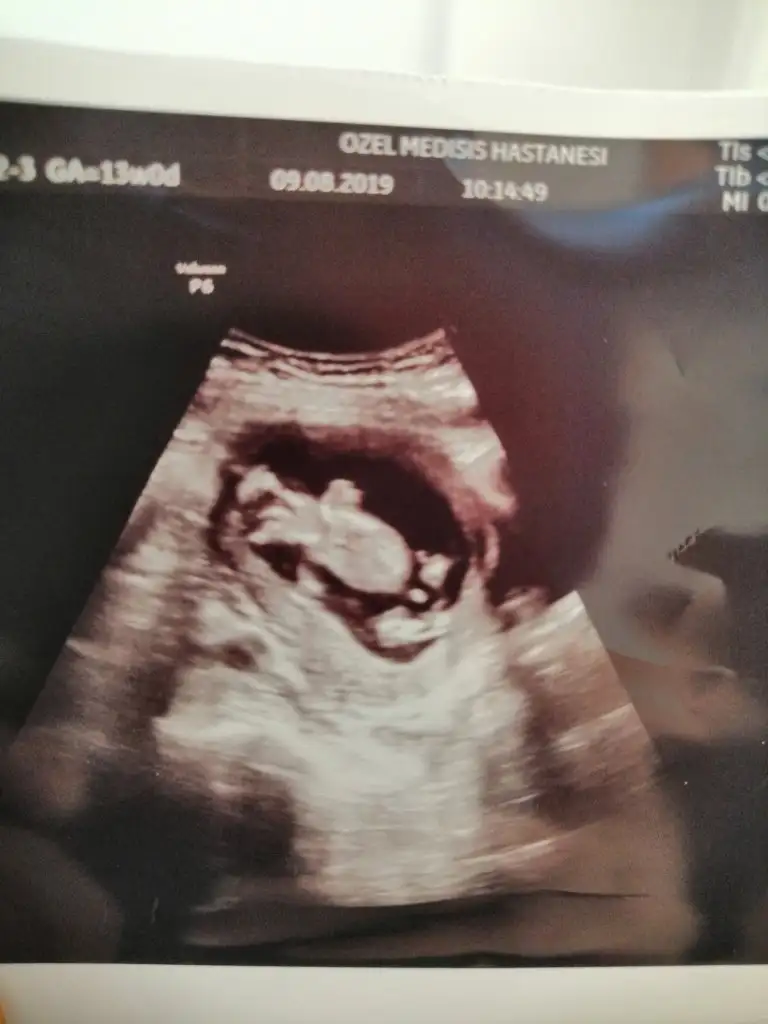

Nub yöntemine göre cinsiyet tahmini

teşekkür ederim var da net değil en yeni ve net olanı bu

Cift yumurtamı tek yumurtamı tekse altaki erkek ustekide erkektir altaki net erkek ustekini tam net değil kız gibi yorumlaya çalıştım hayırlısı olsun sizin için 12+ usg olursa paylaşırsınız ikili tarama için gidecekseniz 12 li usg niz olur sa paylaşın

Çift yumurta ikizi.haftaya gideceğim paylaşırım